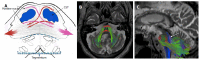

We describe common and less common diseases that can cause magnetic resonance signal abnormalities of middle cerebellar peduncles (MCP), offering a systematic approach correlating imaging findings with clinical clues and pathologic mechanisms. Myelin abnormalities, different types of edema or neurodegenerative processes, can cause areas of abnormal T2 signal, variable enhancement, and patterns of diffusivity of MCP. Pathologies such as demyelinating disorders or certain neurodegenerative entities (e.g., multiple system atrophy or fragile X-associated tremor-ataxia syndrome) appear to have predilection for MCP. Careful evaluation of concomitant imaging findings in the brain or brainstem; and focused correlation with key clinical findings such as immunosuppression for progressive multifocal leukoencephalopahty; hypertension, post-transplant status or high dose chemotherapy for posterior reversible encephalopathy; electrolyte disorders for myelinolysis or suspected toxic-drug related encephalopathy; would yield an appropriate and accurate differential diagnosis in the majority of cases.